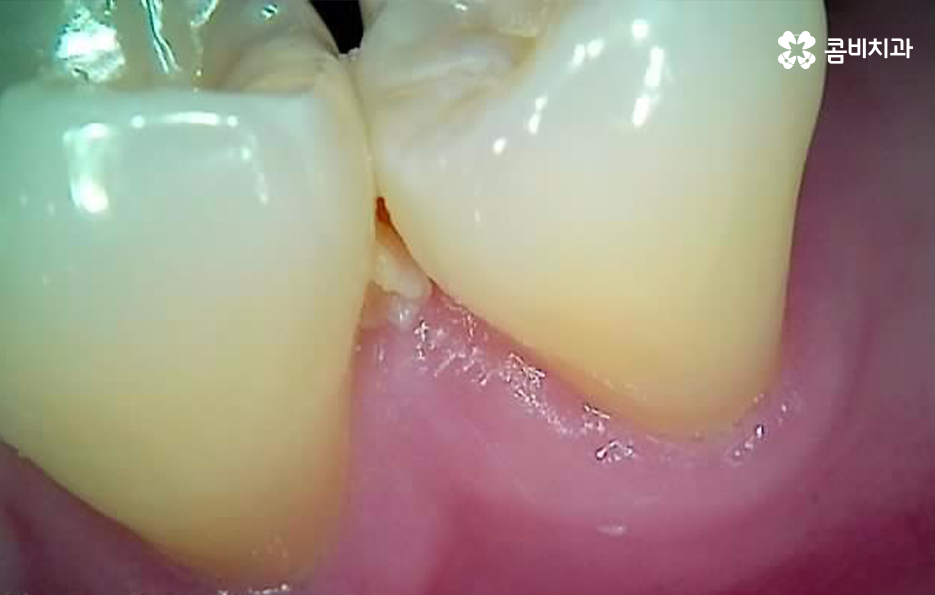

충치는 진행 단계에 따라 법랑질 충치와 상아질 충치, 신경조직의 충치, 뿌리 충치 이렇게 4단계로 구분할 수 있는데요. 쉽게 생각하면 치아의 구조로 볼 때 겉 부분을 이루는 법랑질부터 치아 안쪽으로 충치가 점점 깊어지고 심해지는 단계라고 이해하시면 될 거예요

충치 치료는 이처럼 진행 단계나 충치가 발생한 위치, 깊이 등에 따라 보통 레진, 인레이, 크라운 순서로 치료 방법이 달라지고 있는데요. 그중에서도 충치 신경치료의 경우 통증도 심하고 치료도 여러 진행되며 비용도 비싸다는 인식 때문에 신경치료를 일단 미루고 상태를 지켜보자고 생각하시는 분들도 있어요

충치 신경치료는 언제 하는지 대표적인 사례를 살펴보면 크게 두 가지로 구분할 수 있는데요. 충치가 신경조직에 근접하거나 침범한 경우 진행하는 신경치료가 있고 치아 뿌리 끝에 염증이나 고름 같은 게 생겨서 신경치료를 하는 경우가 있어요